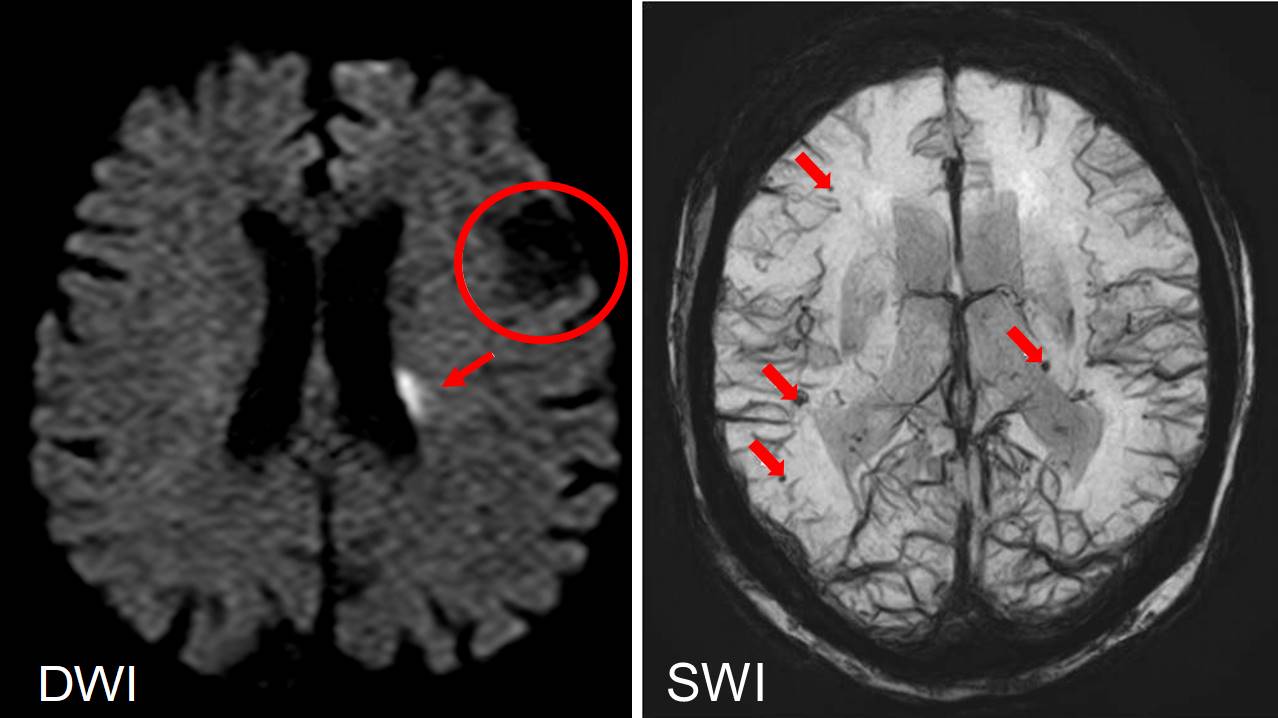

MRI腦部磁振造影檢查

左圖:分子擴散加權影像(DWI),能分辨新舊不同時期發生的中風。腦室旁亮病灶(箭頭處)為急性梗塞性中風,左額葉大面積暗病灶(圓圈處)為陳舊性中風。

右圖:磁敏感加權影像(SWI),可以偵測微出血(箭號處),若有微出血則表示再次發生中風的機會增加。